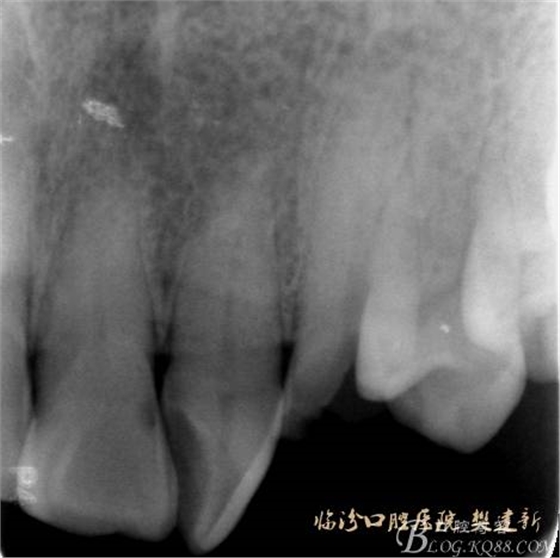

口內(nèi)檢查: 23殘根,位于齦上3MM,根管口探無反應(yīng),叩(+-),無松動,牙周無紅腫.X片示:23根管無阻射,根尖骨密度降低.11.12.13頸部楔形缺損,探敏感,牙髓活力正常.全口牙結(jié)石色素(+).

圖2 治療前X片: 23殘根,根尖區(qū)骨密度降低.